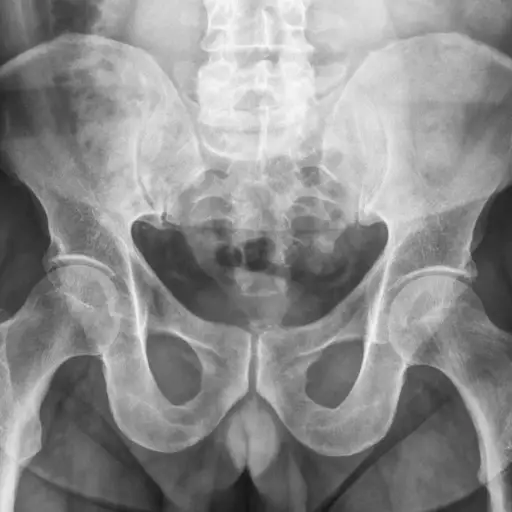

只有在所有其他治疗方法都失败的情况下,手术才被推荐用于ED。它可以考虑在年轻的男性,他们经历过盆腔创伤或男性有重大的解剖问题与他们的阴茎。阴茎植入是其中一种可以考虑的手术。植入物有几种类型,你和你的医生应该决定哪一种是最好的选择。其他手术的选择可能包括对流经骨盆和阴茎的神经或血管进行手术。

一些研究表明,在少数情况下,它可能对锻炼骨盆底肌肉。这是一组围绕在膀胱和直肠下方以及阴茎底部的肌肉。这些练习包括加强和训练用于控制肛门和小便的肌肉。